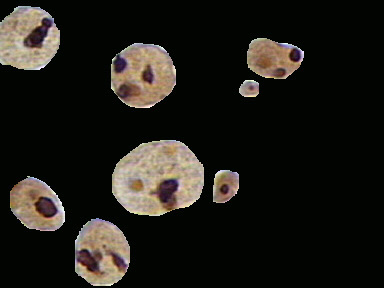

Figura 1. Imagen digitalizada de biopsia de cérvix, diagnosticada de HSIL, con tinción específica para AgNOR (objetivo 100X).

Figura 2. Imagen obtenida a partir de la figura 1 segmentando los núcleos con tinción AgNOR .